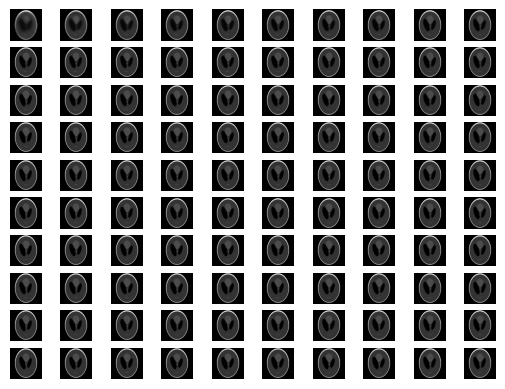

回数を重ねるごとに、元の画像のようになっていく。

単純に元のサイノグラムを再構成するよりも、低ノイズな画像を作れることがある。